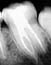

Serie Nº 15 : September 2007